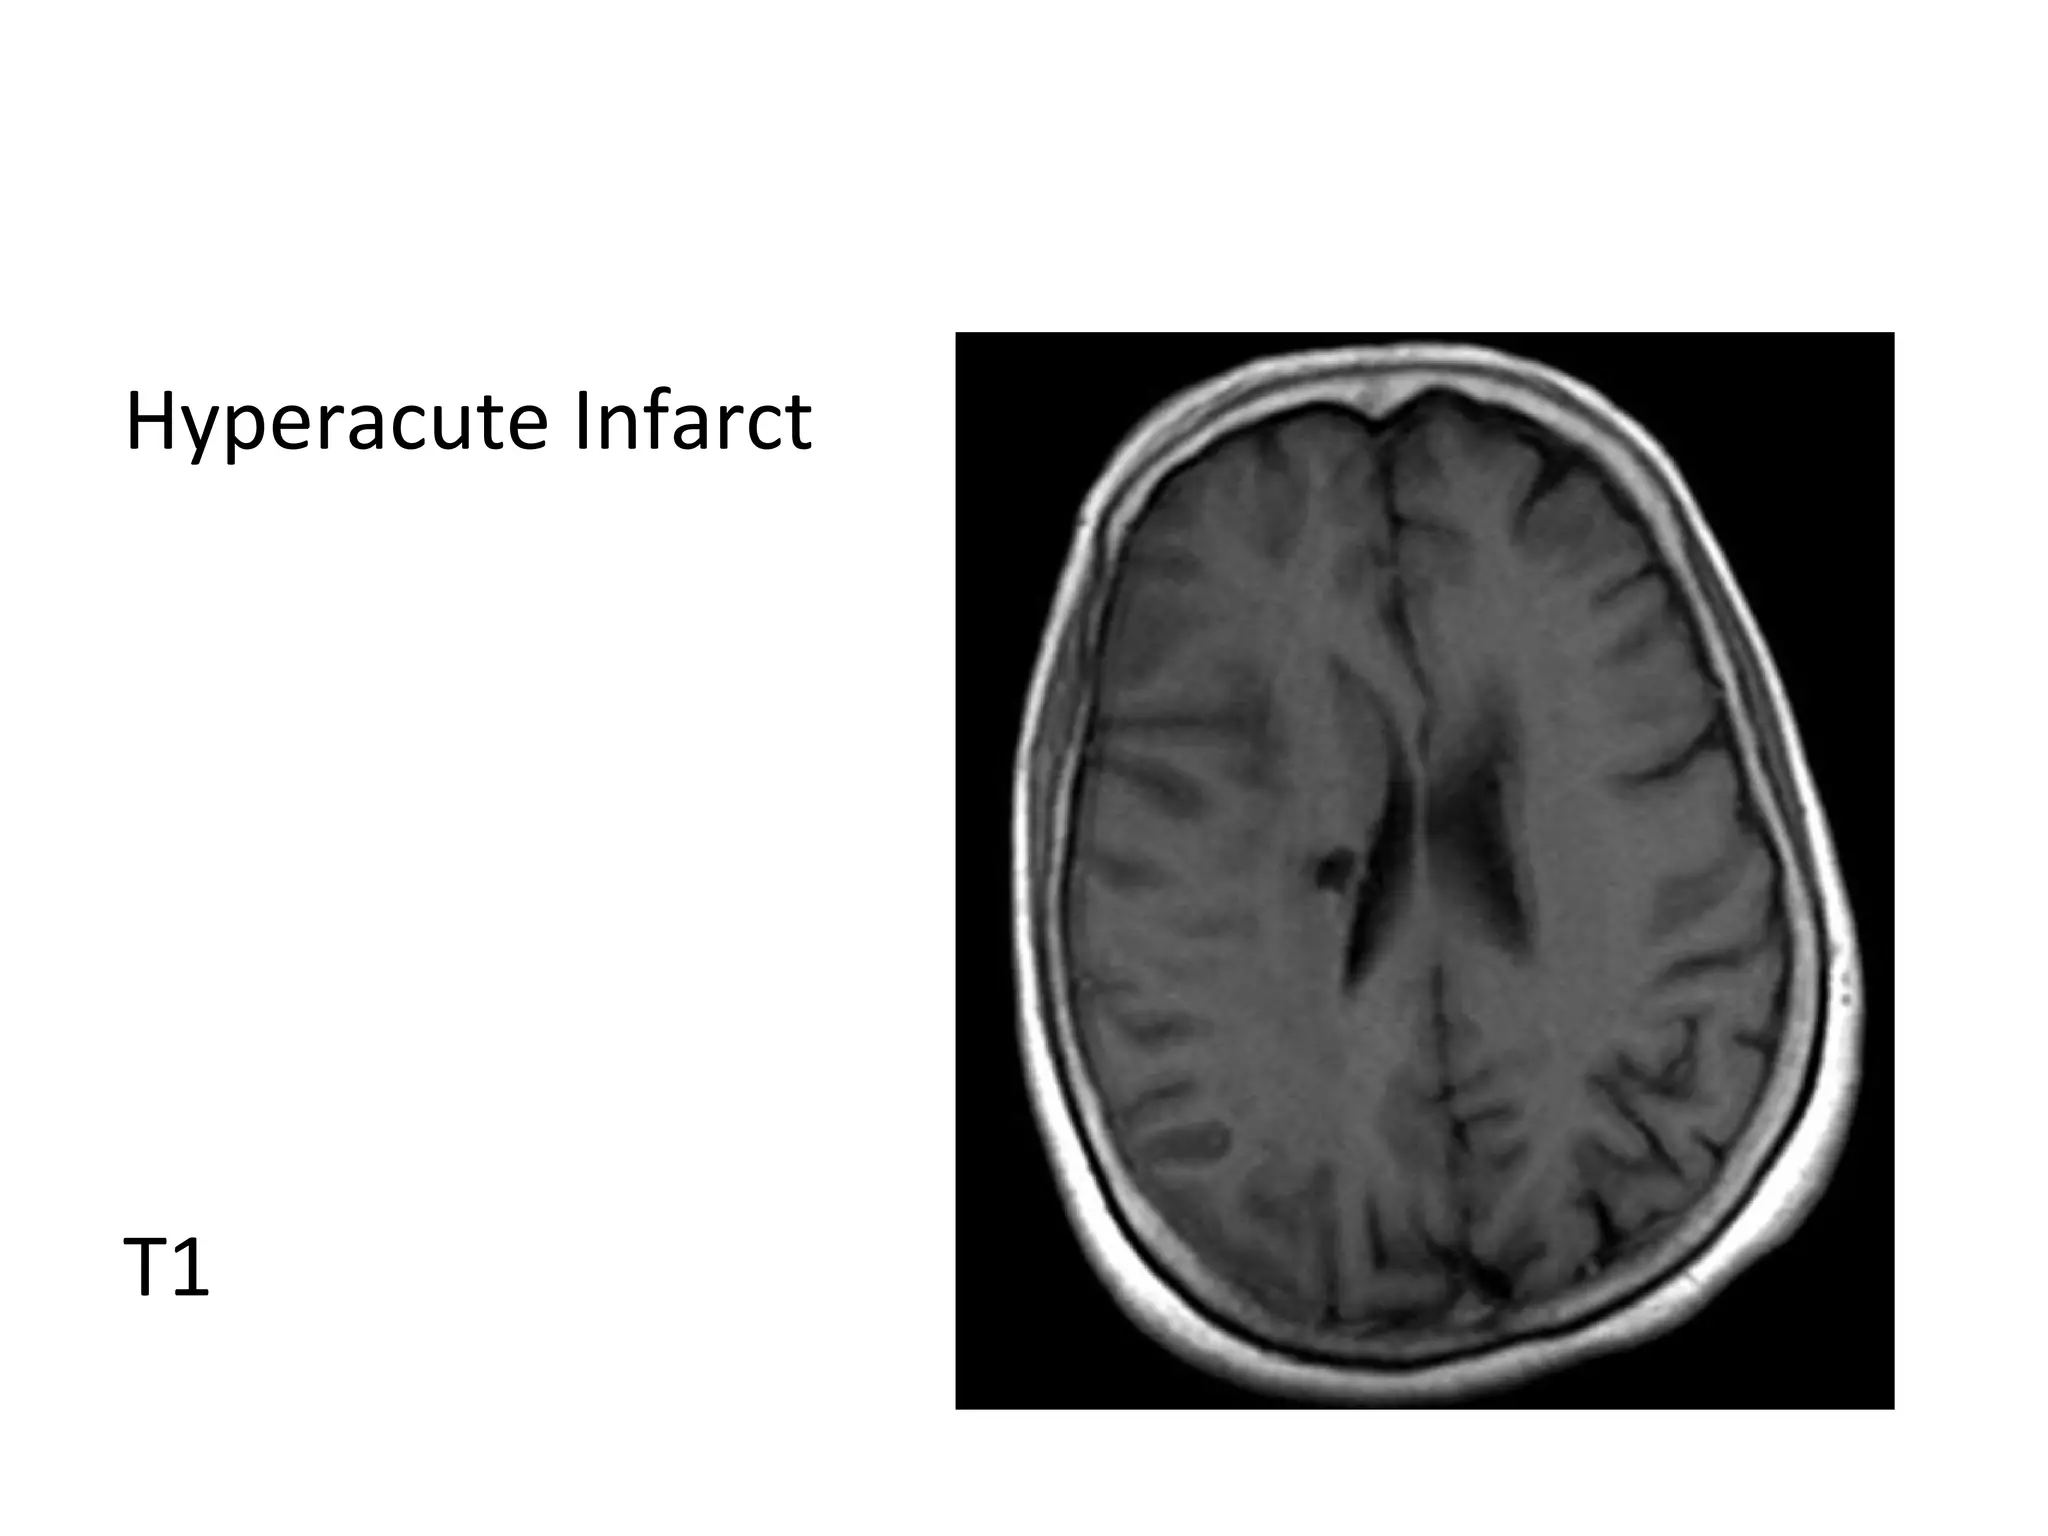

Hyperacute Infarct

T1

a) Hyperacute Infarct (0-6 hours) :

-Within minutes of critical ischemia , the sodium-

potassium ATPase pump that maintains the normal

low intracellular sodium concentration fails , sodium

& water diffuse into cells leading to cell swelling and

cytotoxic edema

-Calcium also diffuses into cells which triggers cascades

that contribute to cell lysis

-Diffusion is the most sensitive modality , DWI

hyperintensity & ADC map hypointensity reflect

reduced diffusivity which can be seen within minutes

of the ictus

-Diffusion is reduced in acute infarct by 2 factors:

1-Shift from extracellular to intracellular water due to

Na/K ATPase pump failure

2-Increased viscosity of infarcted brain due to cell lysis

and increased extracellular protein

-FLAIR may be normal , subtle hyperintensity may be

seen on FLAIR

-Perfusion shows decreased cerebral blood volume of

the infarct core with or without a surrounding region

of decreased cerebral blood flow which represents

the penumbra